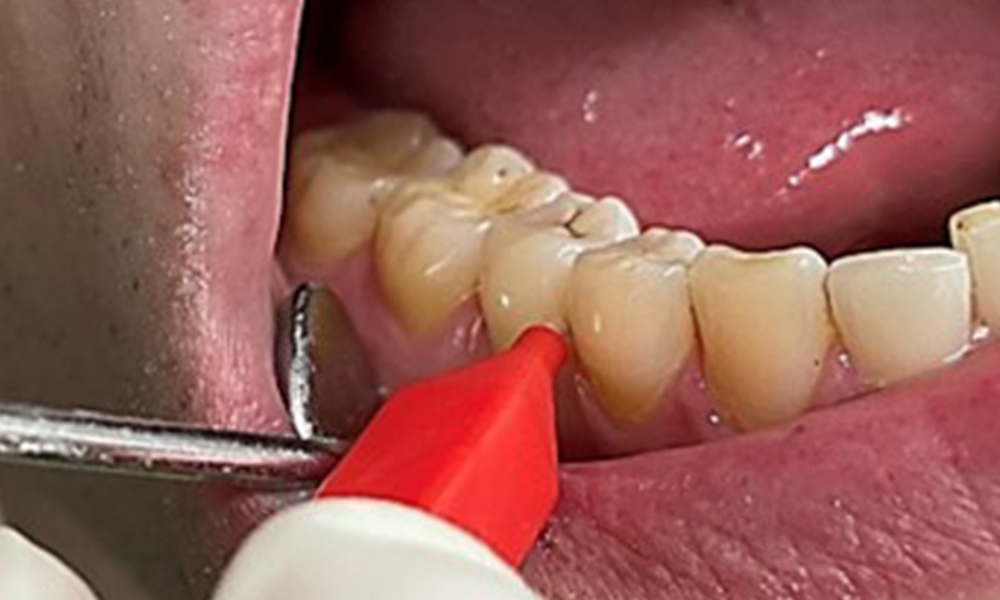

En raison d'un état de santé général par ailleurs favorable, les besoins déterminés lors de l'examen intra-oral seront déterminants pour le traitement. Il sera essentiel de déterminer périodiquement les profondeurs de sondage. Le saignement gingival diminue chez les fumeurs, c'est pourquoi le diagnostic clinique de la parodontite ne peut se faire que par sondage (Fig. 7). En se concentrant exclusivement sur la détermination des indices de saignement, on risque d'occulter une parodontite ou une gingivite existante. (5)

L'état parodontal doit faire l'objet d'un examen approfondi une fois par an. La détection de la plaque dentaire à l'aide d'un agent colorant peut être une source de motivation. L'évaluation des résultats intra-oraux, des surfaces buccales et de la muqueuse linguale est particulièrement importante chez les fumeurs, car elle facilitera la détection de tout changement pathologique à un stade précoce (6). La documentation photographique permet d'évaluer l'évolution des lésions pathologiques potentielles de la muqueuse au fil du temps. Le recours à un spécialiste peut s'avérer nécessaire pour obtenir et tester des échantillons de tissus. Les procédures d'imagerie soutiennent également les discussions motivantes avec le patient. Elles peuvent permettre de mettre en évidence des améliorations au cours des rendez-vous dentaires préventifs ultérieurs.